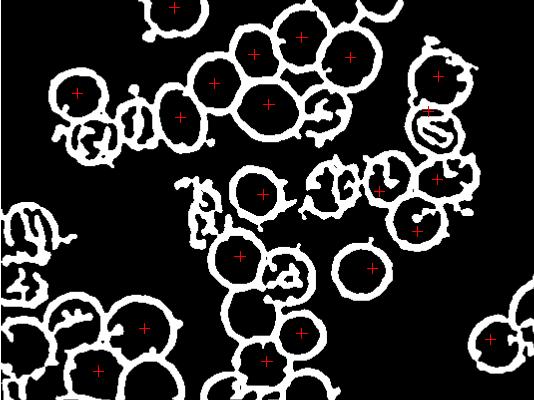

我依靠边缘检测(相对于颜色检测)从血细胞中提取特征。原始图像如下:

我正在使用R EBImage包运行sobel +低通滤波器来实现这样的功能:

plot(imgE)我想知道是否有任何方法来填补大环(血细胞)上的洞,所以它们是实体,有点像:

pp <- locator(type = "p", pch = 3, col = 2) # marked.jpg